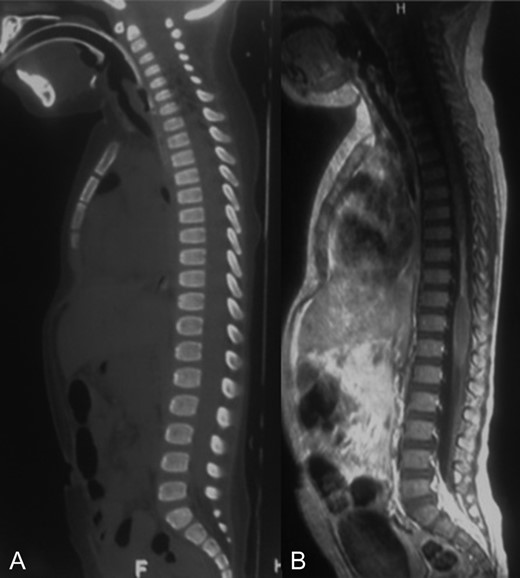

A 2-year-old female patient was referred to our institution after suffering a motor-vehicle accident. She was admitted under sedation with miotic pupils, left iliac hematoma and cervical collar. At admission, brain, chest, abdominal and pelvic CT scans reported right pneumothorax and a hyperdense hepatic lesion. Spine CT scan showed no fracture or any other pathologic findings (Fig. 1A).

A-B: A. Sagittal bone window of spine showing normal alignment and no fracture. B. Sagittal T1 contrast enhanced sequence showing a narrowed spinal cord from T7 to T10 that could correspond to gliosis and edema.